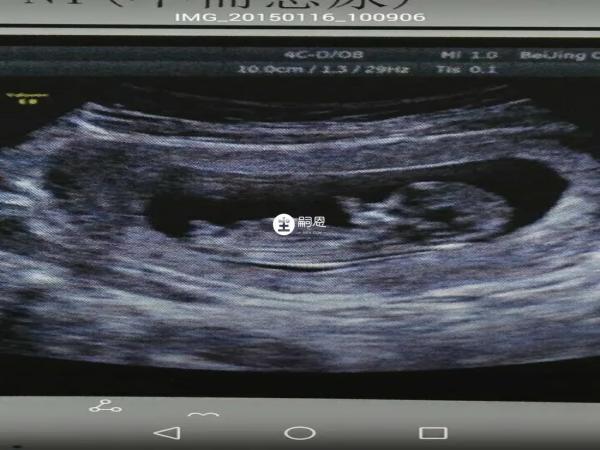

在产检时若医生说孕妇羊水少,其并是在暗示男孩或女孩,羊水量与胎儿的性别没有关联,羊水是指女性怀孕时,子宫羊膜腔内的液体,对于胎儿的生长发育也起着至关重要的作用,羊水的来源、量以及成分与孕周有关,当羊水量小于300ml时称为羊水过少,羊水少可能是胎儿畸形、胎盘功能不全所致。

首先,羊水偏少是不可能和孩子的性别有关,因为这种情况是不科学的,所以在出现羊水偏少时,是不可能判断出孩子的性别,而羊水少可能是胎儿结构异常、胎盘功能减退、羊膜病变、母体因素等原因造成的,如果胎儿泌尿系统存在异常引起的,比如肾小管发育不全、输尿管梗阻等,会导致胎儿尿液减少,从而造成羊水减少情况。

5、医生说羊水少指胎儿不稳非男女暗示